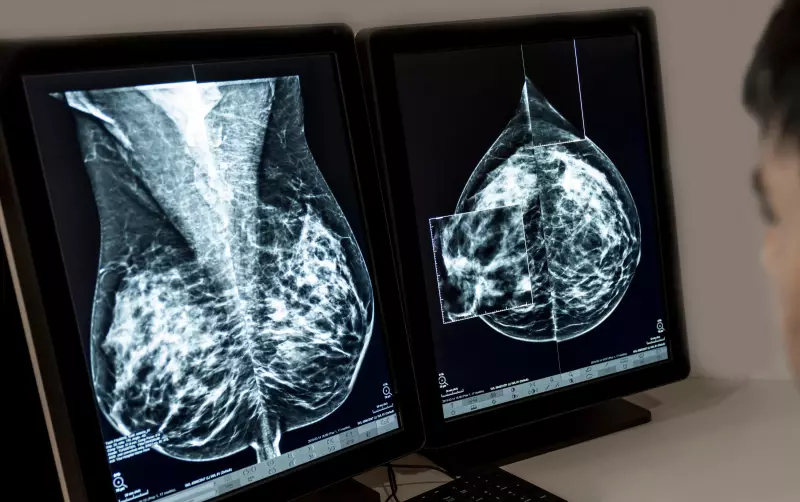

A história é daquelas que dão vontade de bater na mesa. A funcionária tinha um contrato de trabalho que ia até agosto de 2023, mas em março do mesmo ano descobriu o câncer. Começou o tratamento imediatamente, com todo aquele processo difícil que quem já passou por isso conhece bem: quimioterapia, os efeitos colaterais, a exaustão física e emocional.